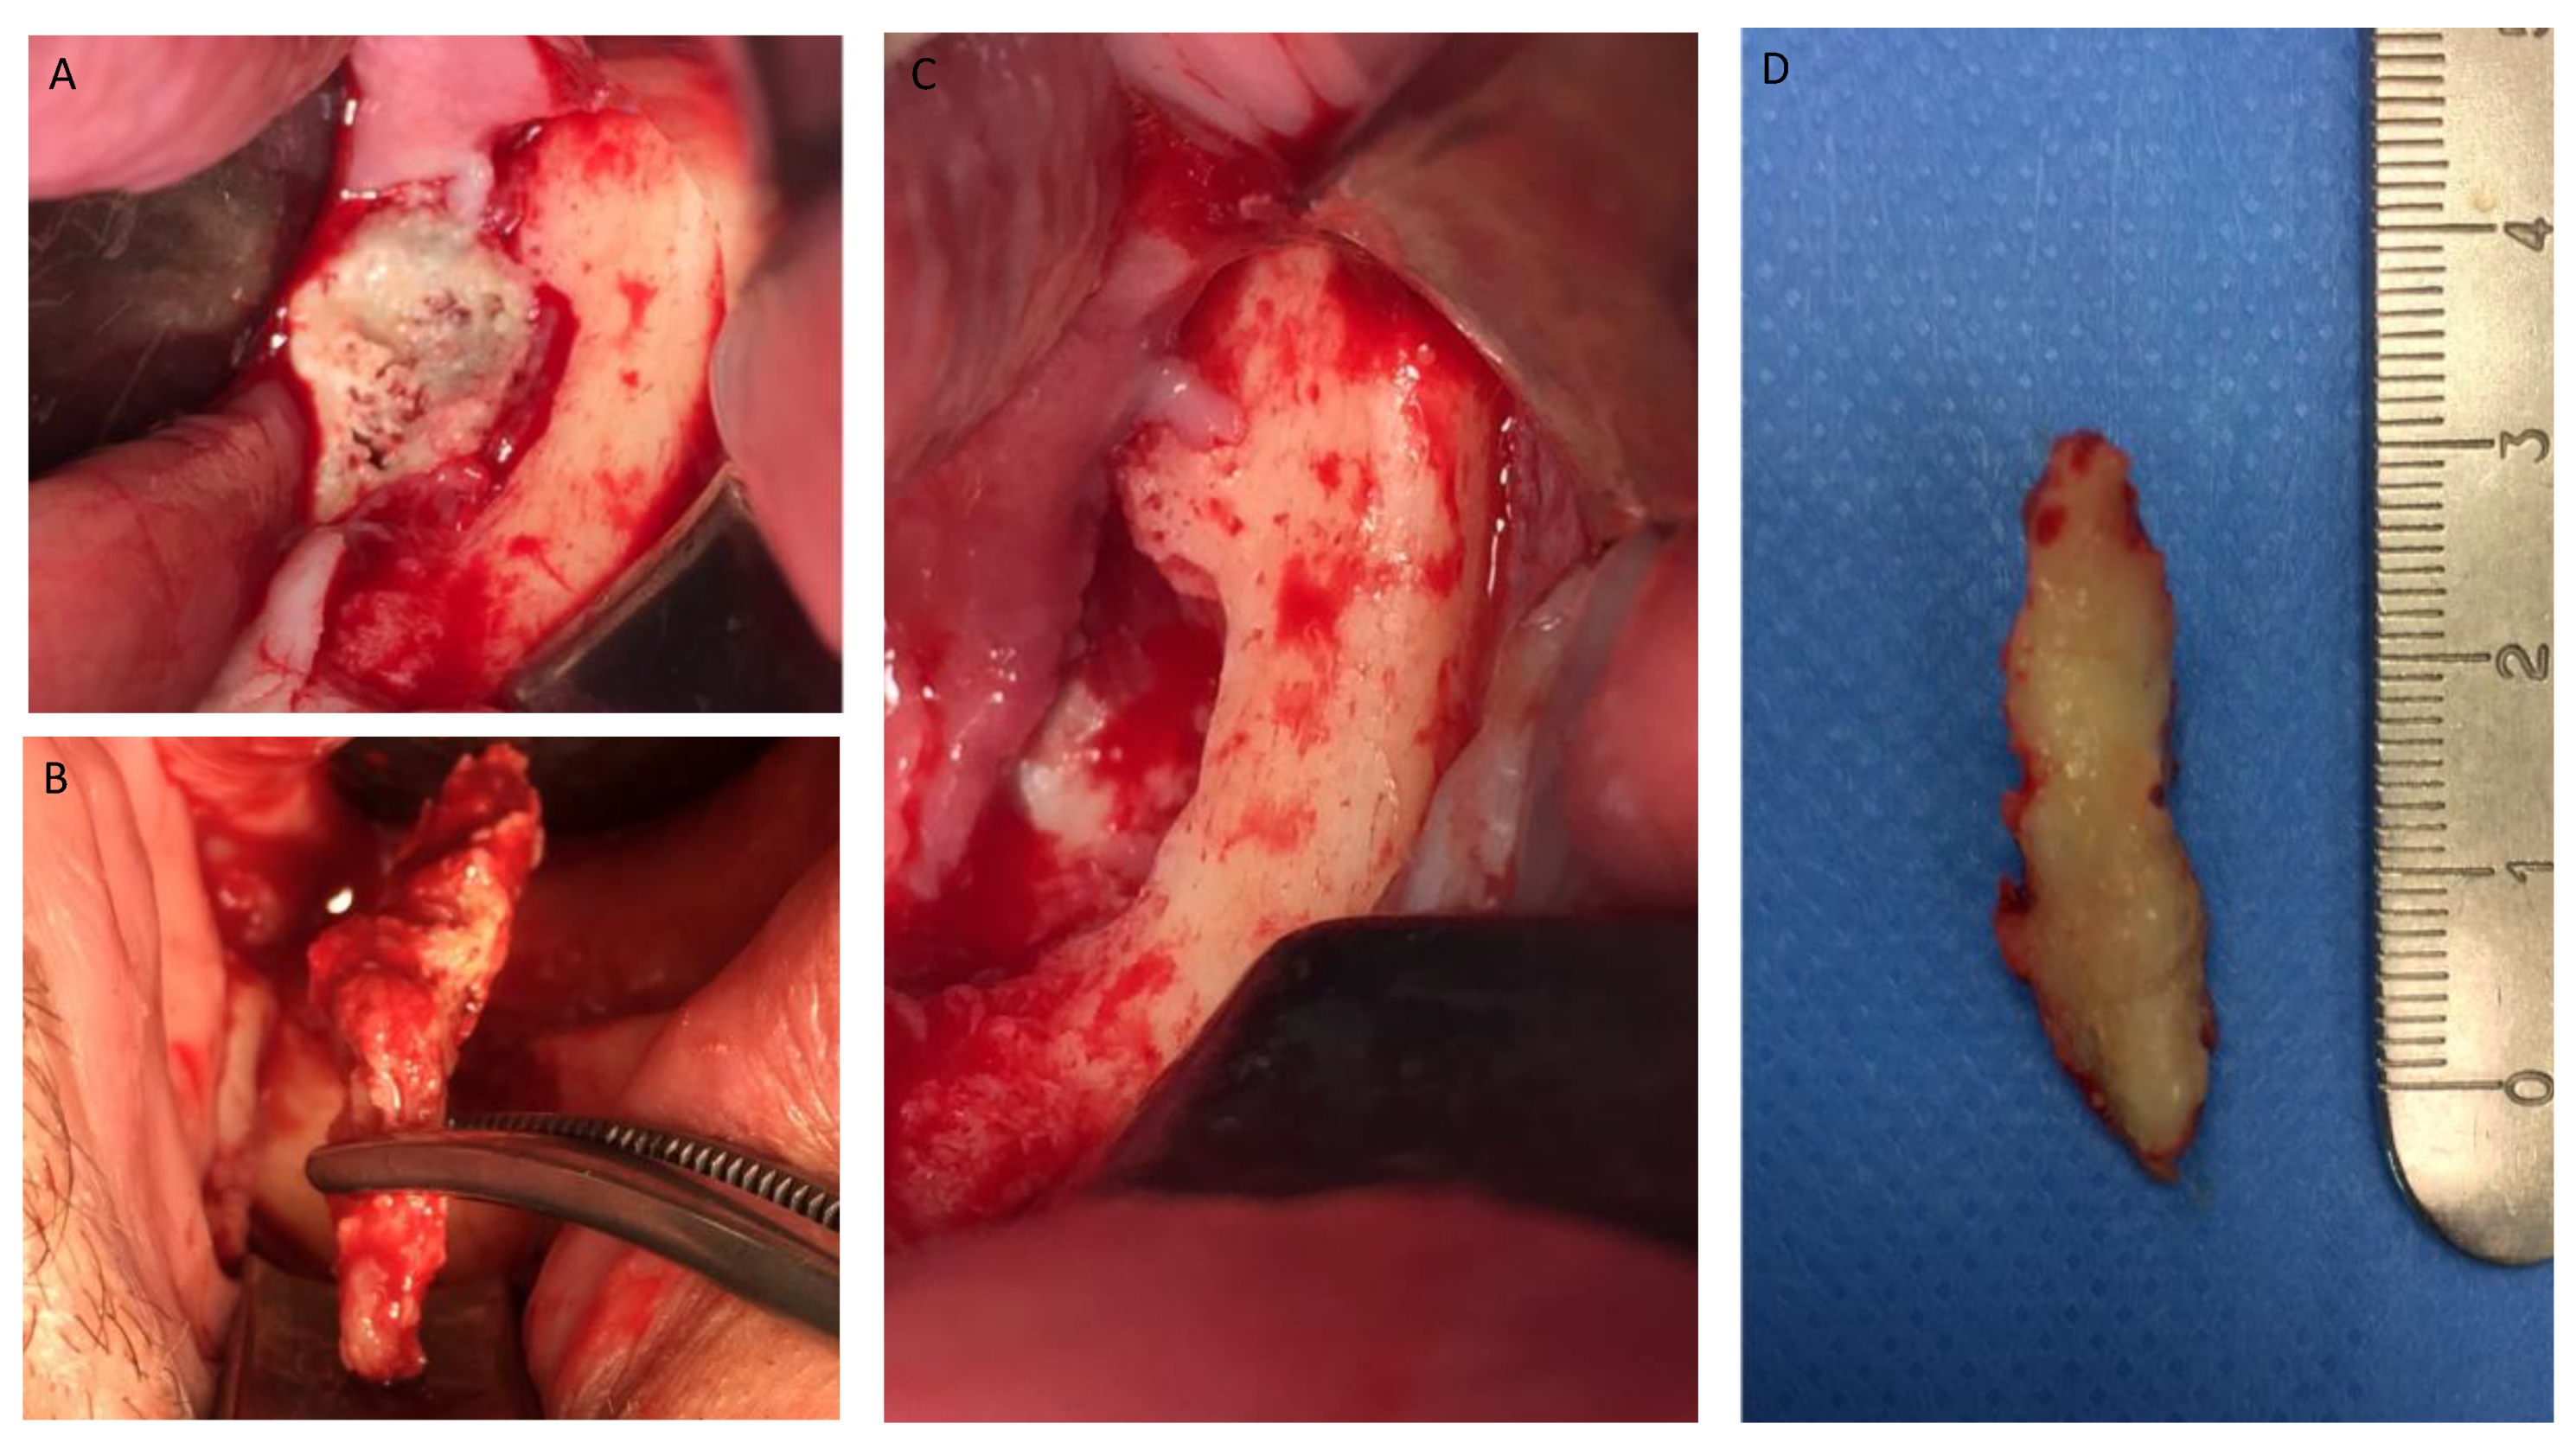

Figure 1, Figure 2, Figure 3, Figure 4, Figure 5, Figure 6 and Figure 7 show the progress of treatment in one of the patients of the test group. In Figure 3 reduction of the medullar space is visible, that may create a chronic ischemic area susceptible to necrosis.

Figure 4.

(A–D) Intra-operative view showing operation steps and resected osteonecrotic tissue from the right side of the mandible. After pharmacological preparation with pentoxifylline and tocopherol, the cleavage plane created by the reactive granulation tissue can be clearly seen which tends to separate the necrotic tissue from the healthy bone. Sequestrectomy was made using an osteotome to obtain the necrotic specimen. After the debridement, the bottom of the surgical area was bleeding properly, which creates a favorable environment for healing.